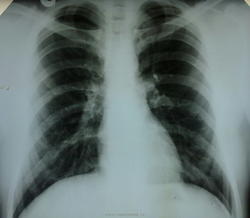

Пациенту 21 год, проходил ежегодную диспансеризацию, в ходе которой выявлена следующая картина в легких.Сделали ЛТ, обследовали и в Обл.туб на КЭК с диагнозом :туберкулома верхней доли левого легкого.На 3-4 месяца он выпал из поля зрения, на днях появился-счастливый и довольный.Его долго обследовали в вышестоящих ЛУ, подозревали даже рак верхнедолевого бронха( говорит, что чуть не поседел), а оказалась туберкулома ( все как положеноКТ,-гистология).Лично смотрела выписки одного из Московских ЛУ.Доволен был нашим отделением, так как много раз проходил ФОГК во время обучения в одном из учебных учреждений где-то в Центральных районах страны,причем буквально за пару-тройку месяцев до прибытия в нашу область.Теперь мы для него как полубоги.

очаговая тень в S1 слева до 2.0 см, учитывая кальцинаты в корнях и в\легочных полях и здесь же фиброз, отнесем-ка ее к твс